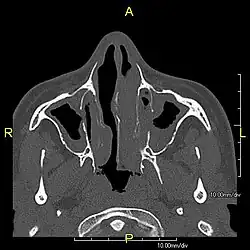

| Complications | Chronic recurrent respiratory infections, including sinusitis, bronchitis, pneumonia, and otitis media.[2] |

Around 80% of people with primary ciliary dyskinesia experience respiratory problems beginning within a day of birth. Many have a collapsed lobe of the lung and blood oxygen low enough to require treatment with supplemental oxygen.[1] Within the first few months of life, most develop a chronic mucus-producing cough and runny nose.[1] The main consequence of impaired ciliary function is reduced or absent mucus clearance from the lungs, and susceptibility to chronic recurrent respiratory infections, including sinusitis, bronchitis, pneumonia, and otitis media. Progressive damage to the respiratory system is common, including progressive bronchiectasis beginning in early childhood, and sinus disease (sometimes becoming severe in adults). However, diagnosis is often missed early in life despite the characteristic signs and symptoms.[2] In males, immotility of sperm can lead to infertility, although conception remains possible through the use of in vitro fertilization, there also are reported cases where sperm were able to move.[8] Trials have also shown that there is a marked reduction in fertility in females with Kartagener's syndrome due to dysfunction of the oviductal cilia.[9]

Many affected individuals experience hearing loss and show symptoms of otitis media which demonstrates variable responsiveness to the insertion of myringotomy tubes or grommets. Some patients have a poor sense of smell, which is believed to accompany high mucus production in the sinuses (although others report normal – or even acute – sensitivity to smell and taste). Clinical progression of the disease is variable, with lung transplantation required in severe cases. Susceptibility to infections can be drastically reduced by an early diagnosis. Treatment with various chest physiotherapy techniques has been observed to reduce the incidence of lung infection and to slow the progression of bronchiectasis dramatically. Aggressive treatment of sinus disease beginning at an early age is believed to slow long-term sinus damage (although this has not yet been adequately documented). Aggressive measures to enhance clearance of mucus, prevent respiratory infections, and treat bacterial superinfections have been observed to slow lung-disease progression. The predicted incidence is 1 in approximately 7500.[10]

Several diagnostic tests for this condition have been proposed.[5] These include nasal nitric oxide levels as a screening test, light microscopy of biopsies for ciliary beat pattern and frequency and electron microscopic examination of dynein arms, as the definite diagnosis method. Genetic testing has also been proposed but this is difficult given that there are multiple genes involved.[6]